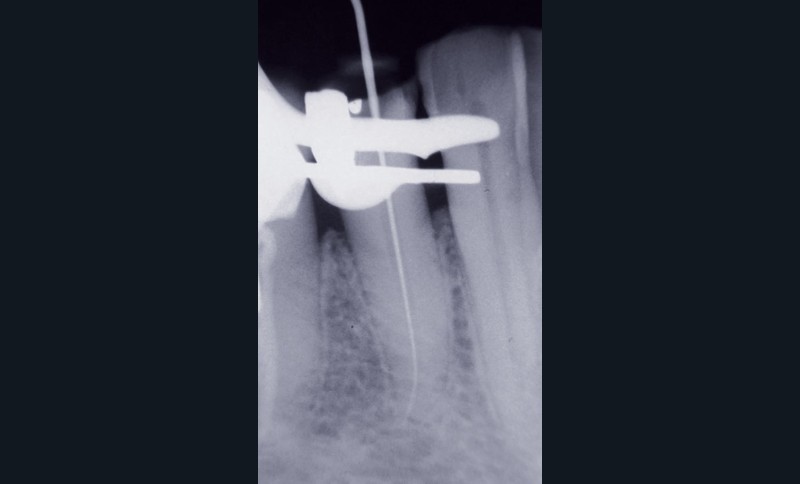

– sur le plan radiographique, on note l’absence de toute parodontite à proprement parler « apicale », alors que l’on observe sa présence en situation latéro-radiculaire ;

– on relève la présence d’un hiatus de l’ancrage prothétique situé entre l’extrémité de l’ancrage et l’obturation apical du canal ;

– la situation latérale de la lésion suggère un rapport direct de celle-ci avec le hiatus de l’ancrage canalaire observé.